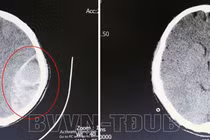

(khoahocdoisong.vn) - Bé 4 tuổi chạy chơi không may ngã vào nền cứng bị chấn thương sọ não phải mổ cấp cứu mở nắp sọ lấy máu tụ ngoài màng cứng. Cha mẹ cần chú ý khi cho trẻ chơi.